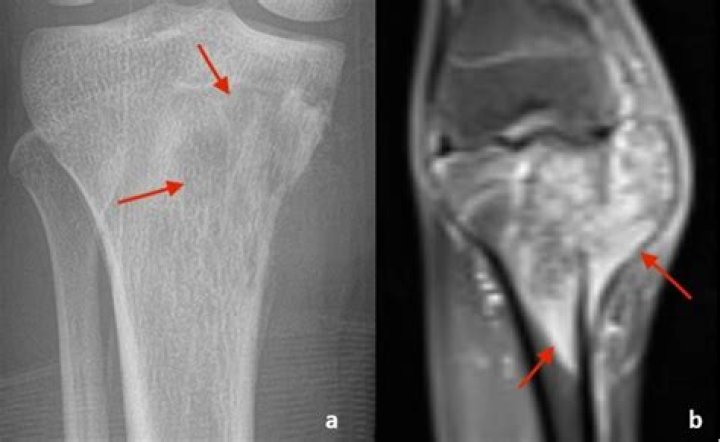

Can you tell if a tumor is benign with an MRI?